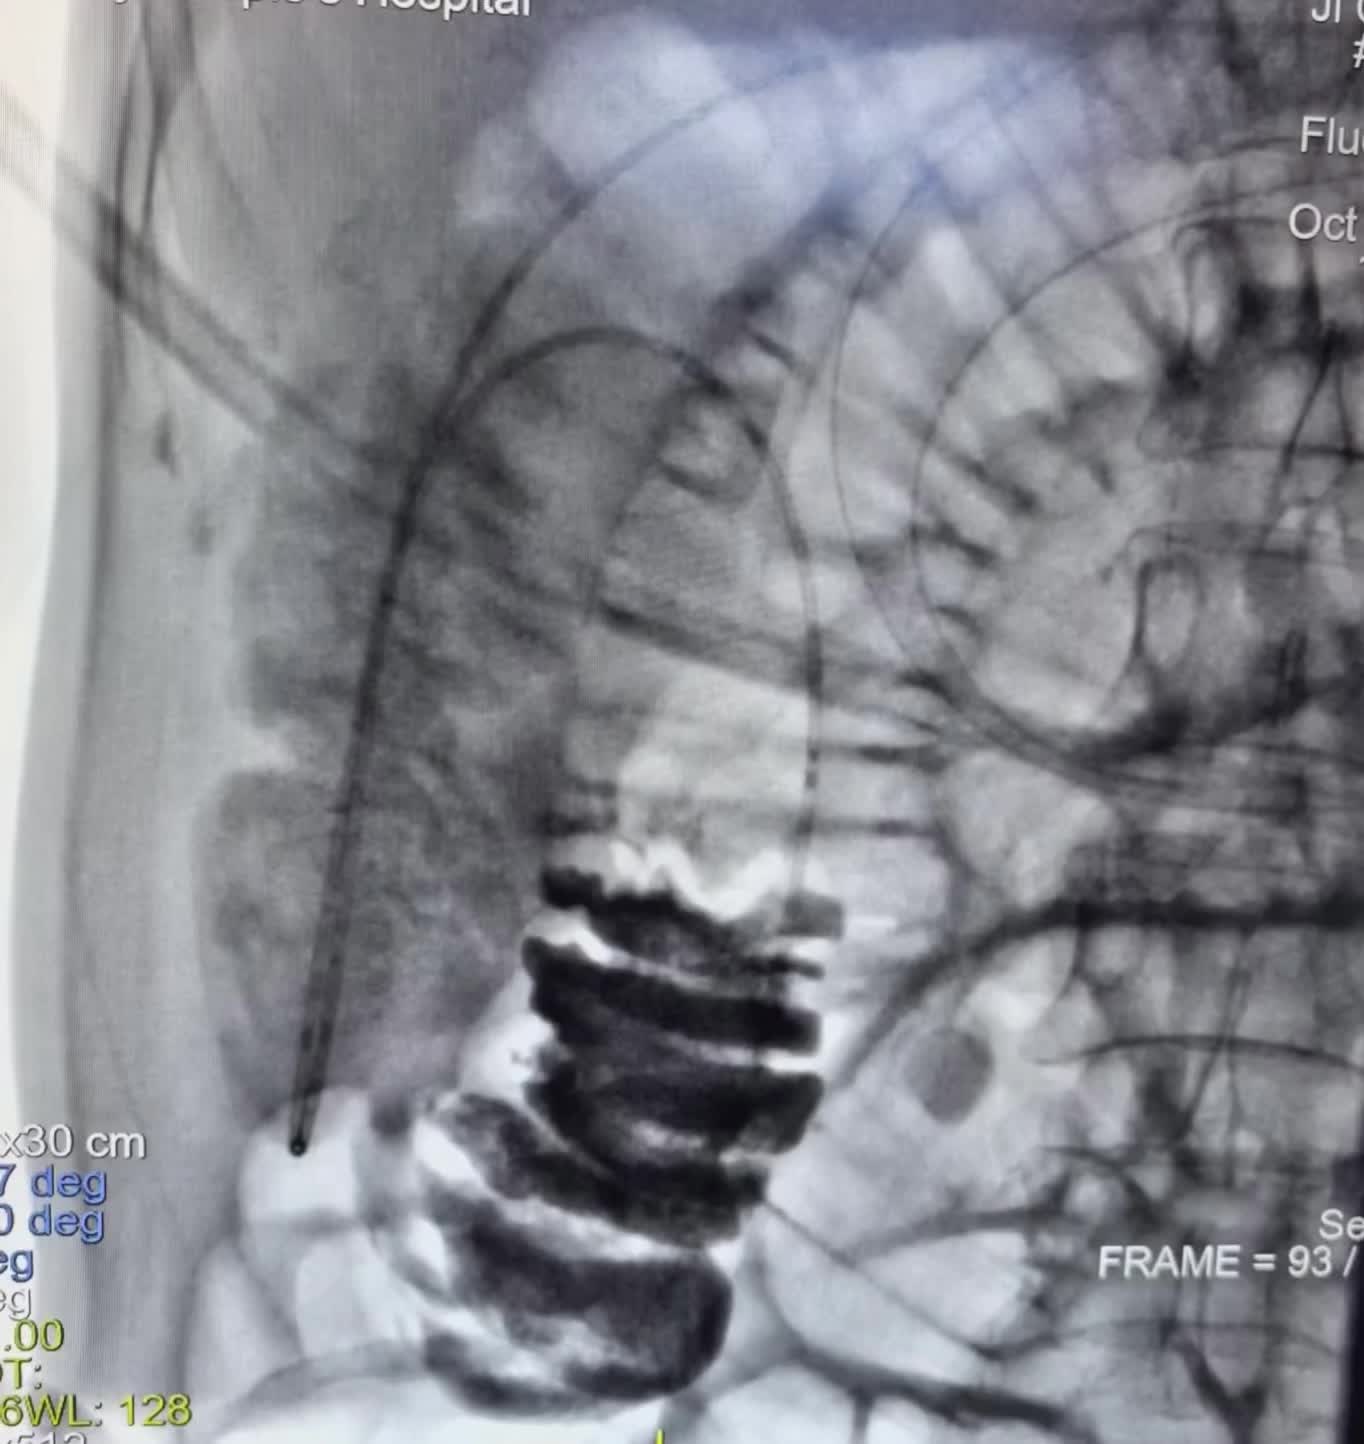

直肠癌术后3年,近期反复肠梗阻,胃管减压 直肠癌术后3年,近期反复肠梗阻,胃管减压1周,效果欠佳。今日在DSA可视化行肠管黏连松紧,及肠道减压管置入,直肠吻合狭窄扩张术,术后即可通便通气,腹胀,腹痛即可减轻。口。DSA可视化经鼻经肛双向开通,松解黏连介入治疗技术,安全有效,经自然腔道无创操做效果立竿见影。